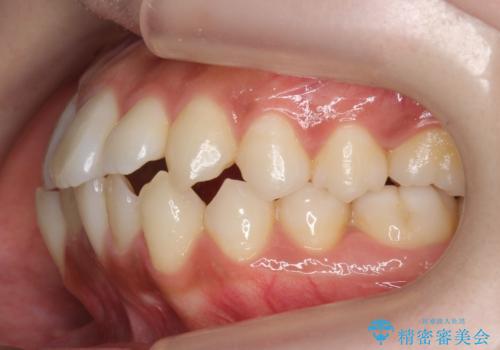

犬歯が歯ぐきにうまっている 真ん中のずれ、出っ歯を治したい

- 出っ歯を主訴に来院。

右上の犬歯が内側に生えていました。

右上の半分埋まっている犬歯を抜歯し、残り上下左右3本抜歯してワイヤー矯正を行いました。

前歯が斜めになっているのもだいぶ改善しました。